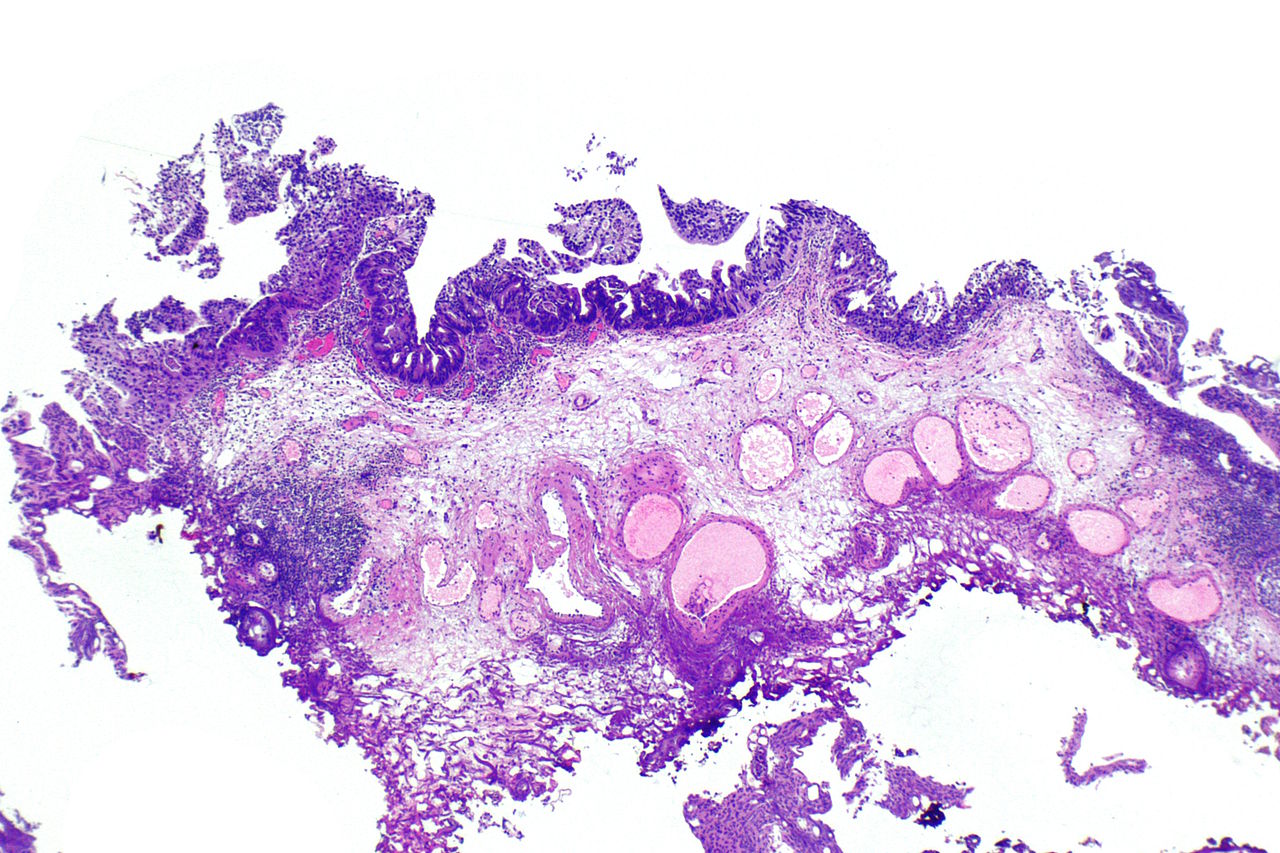

Фотографии опухоли медуллярной аденокарциномы

Раздел: Снимки-откровения